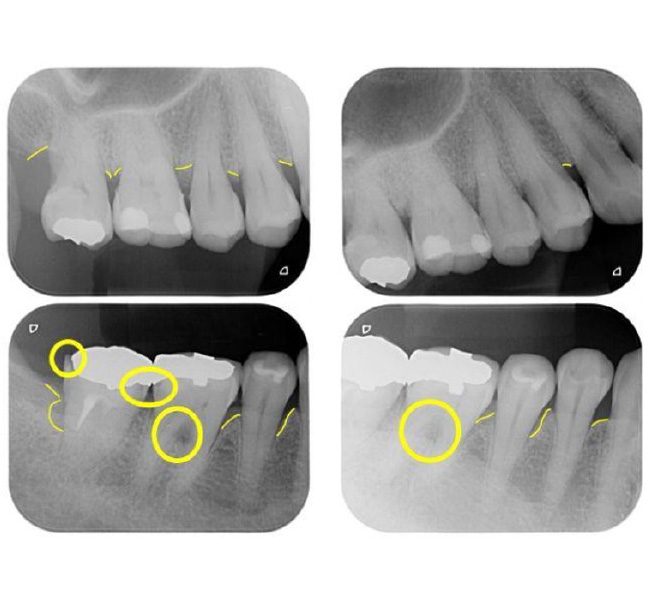

治療前

| 主訴 | 左奥歯が仕事が忙しくなると上下とも痛くなる。 毎月メインテナンスしていた歯科医院が閉院した。 歯周病含め今の状態が気になる。 全体のメインテナンスもしたい。矯正治療はやりたくない。 |

| 治療内容 | 全顎治療:歯周病治療、根管治療、 歯肉弁剥離掻爬術(フラップ手術)、 セラミック治療、ダイレクトボンディング |